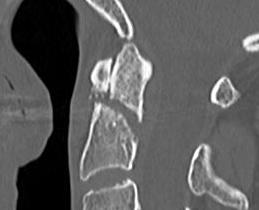

Type III

Definition

Through the body of C2

May involve portions of C1 or C2 facets

High healing potential

Non operative management

- 212 patients with Type III dens fracture

- average age 72, 20% lived independently

- 95% treated nonoperatively

- 5% required surgery

- 25 patients with Type III dens fracture

- hard collar or halo vest

- 22/25 (88%) united

- nonunion associated with increased coronal tilt and lateral mass gap > 2mm